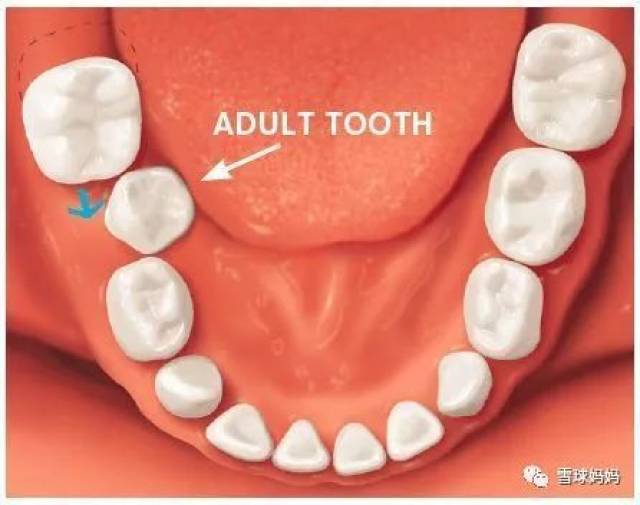

- 导致宝宝恒牙长不出,或者一长出来就有缺损.

- 8成孩子都蛀牙 小心长不出恒牙

- 牙龋齿严重影响了恒牙牙胚,长出来的恒牙你觉得还能健康吗